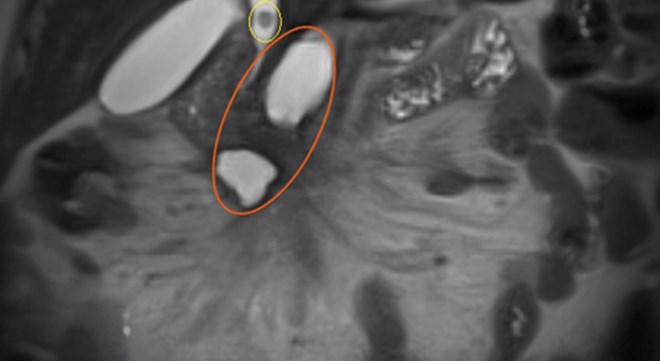

Thông thường, những trường hợp này được nội soi mật tụy ngược dòng (ERCP) để lấy sỏi ở ống mật chủ, đồng thời cắt túi mật nội soi. Tuy nhiên, trường hợp bà N.T.H, do khối hoại tử thành hóa ở vùng đầu tụy đè hẹp, biến dạng tá tràng, không thể tiếp cận để kéo sỏi ống mật chủ qua nội soi mật tụy. Bà được phẫu thuật nội soi cắt túi mật, đồng thời xẻ ống mật chủ để lấy hai viên sỏi ở ống mật chủ.